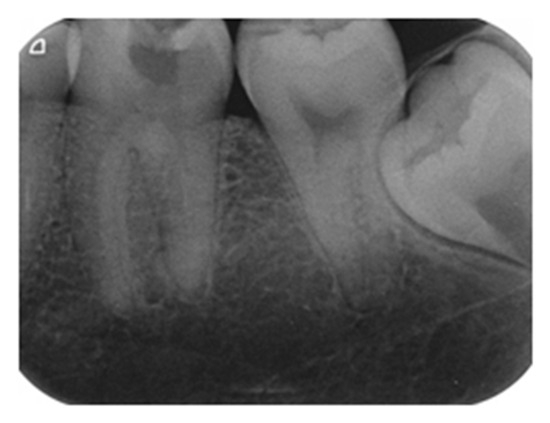

- Demant, S.; Dabelsteen, S.; Bjørndal, L. A macroscopic and histological analysis of radiographically well-defined deep and extremely deep carious lesions: Carious lesion characteristics as indicators of the level of bacterial penetration and pulp response. Int. Endod. J. 2021, 54, 319–330. [Google Scholar] [CrossRef]